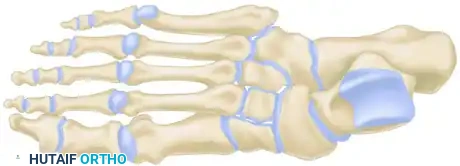

Myerson Classification

Classification facilitates communication and helps determine the vector of displacement, though it is not strictly prognostic. Myerson’s modification of the original Quénu and Küss classification is the academic standard:

- Type A (Total Incongruity): Displacement of all five metatarsals, with or without a fracture of the second metatarsal base. Displacement is typically lateral or dorsolateral, moving as a single unit (homolateral).

- Type B (Partial Incongruity): One or more articulations remain intact.

- Type B1: Medial displacement, often involving the intercuneiform or naviculocuneiform joint.

- Type B2: Lateral displacement, which may involve the first metatarsal-cuneiform joint.

- Type C (Divergent): The first metatarsal displaces medially while the lesser metatarsals displace laterally.

- Type C1: Partial divergent.

- Type C2: Complete divergent. These are high-energy injuries associated with massive soft tissue swelling and a high risk of compartment syndrome.